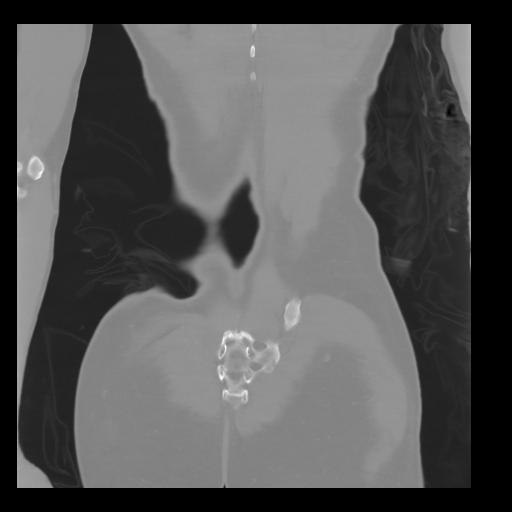

35 CUERPO,CE,Coronal,3.000,CUERPO,Coronal,